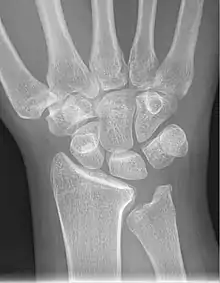

X-ray showing stage IIIB on right wrist, with ulnar impingement.